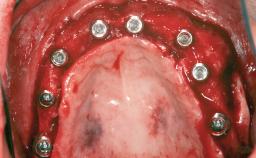

A 46-year-old woman was referred for treatment whose main complaints were mobility of her fixed partial dentures (right maxilla and left mandible) and periodontal bleeding during function. She also reported having taken systemic antibiotics to treat recurrent swelling in the area of the upper left molars. The patient had not seen a dentist for at least 2 years. She did not smoke and had no history of major systemic disease other than two minor orthopedic procedures some years back. The first-visit examination revealed poor plaque control, tooth mobility, periodontal disease, and a residual dentition widely associated with deep periodontal pockets.

| # of Implants | 3 |

| Bone Augmentation | Horizontal|Staged|Vertical |